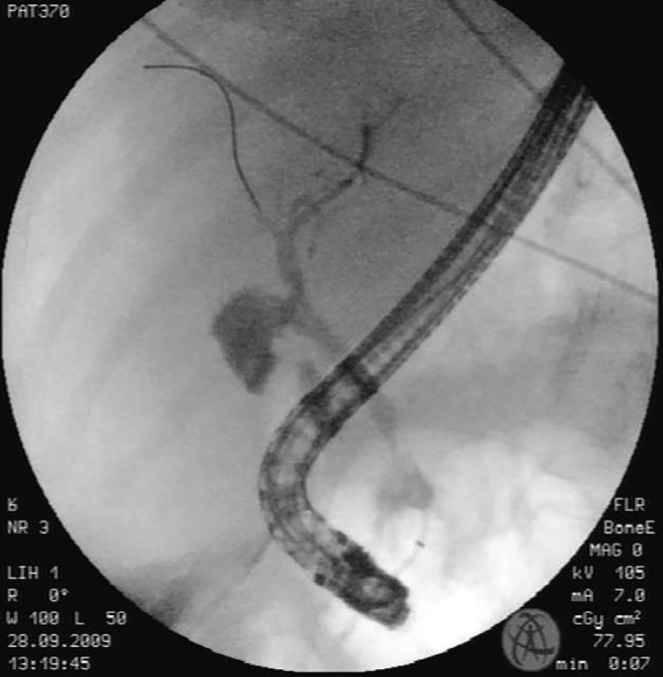

Endoscopic biliary stenting is a widely adopted technique for managing bile duct injuries post-cholecystectomy. However, its complications can have severe consequences. Although rare compared to other endoscopic retrograde cholangiopancreatography-related complications, duodenal perforation due to stent migration carries a significant risk of morbidity and mortality. While biliary stenting is often considered a less invasive alternative to surgery, timely recognition and management of potential complications remain crucial. We present a case of duodenal perforation due to biliary stent migration in a 49-year-old woman following laparoscopic cholecystectomy, emphasizing the effectiveness of conservative management, including the key role of interventional radiology, in selected patients.

Abstract Image